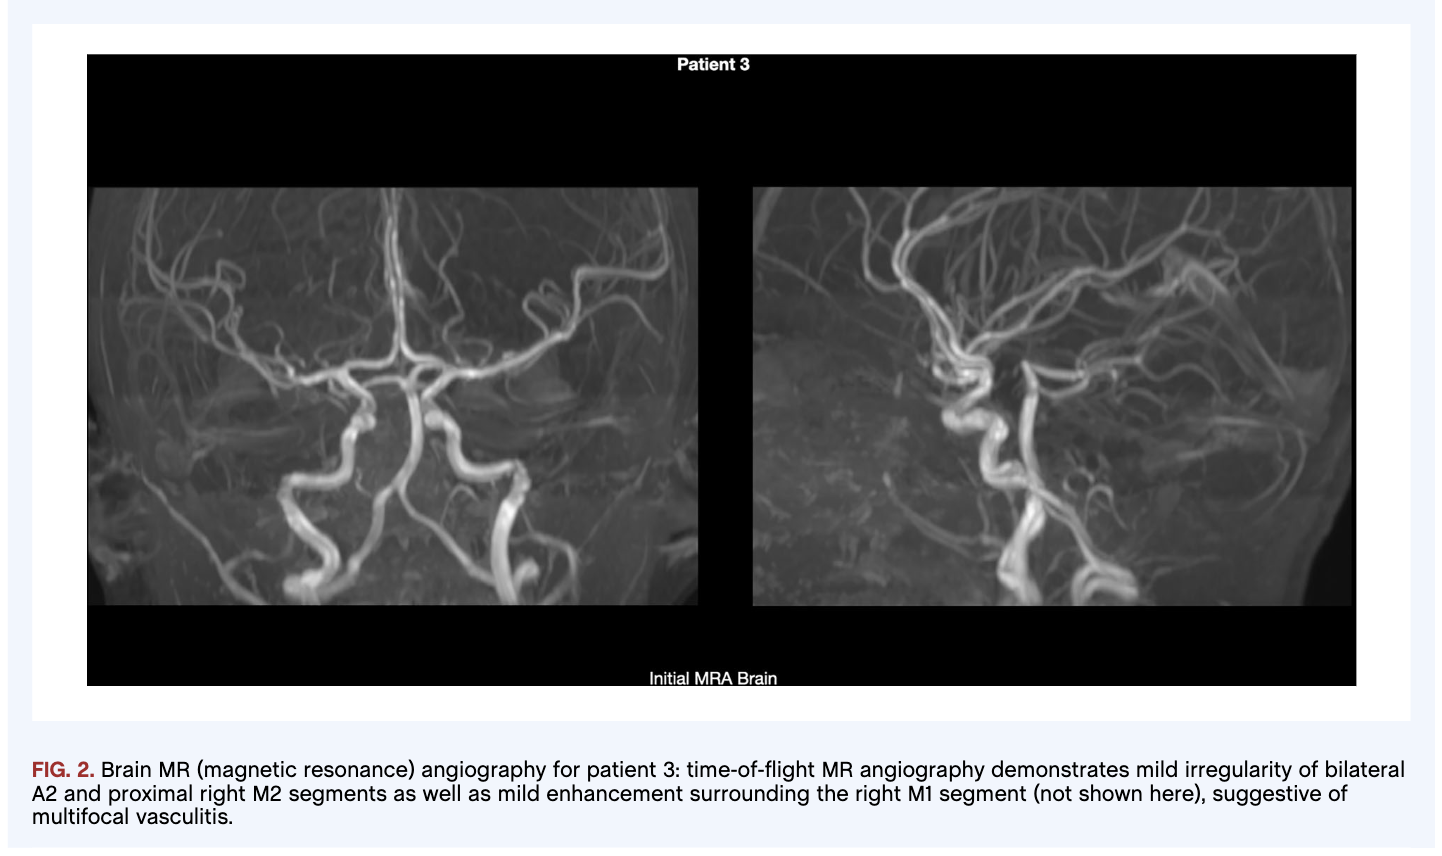

Results: We observed subcortical myoclonus and progressive generalized dystonia (Patient 1), transient dyskinesias and refractory focal dystonia (Patient 2), and generalized dystonia evolving into chorea and lingual dyskinesias (Patient 3). One patient displayed multifocal vasculitis on MRI angiography, a novel finding. All patients demonstrated bilateral T2 hyperintensities in the basal ganglia on MRI. In the acute period, all patients received high-dose corticosteroids, with two also receiving IVIG, interventions which have been posited to promote clinical improvement. Two patients required admission for management of worsening dystonia after their acute presentation. All patients required multiple treatments for dystonia and chorea throughout their disease courses, highlighting the refractory nature of their movement disorders.

Figure 2.